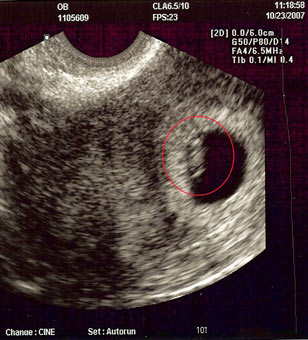

Two of the most powerful weapons in the Conservative arsenal – and both are radical game changers–have been virtually ignored by reproductive rights strategists: ultrasound and fetal photography. Thirty years ago, pregnancy was a black box. Sperm went in, babies came out. Today a pregnant mother is given beautiful books of fetal images so that she can track and marvel at the process of development going on inside her. Doctors’ visits often include an ultrasound that is oooh-ed over by a pair of curious parents-to-be. Part of what made my own abortion painful was that my husband and I had seen an image of our developing fetus, our child-to-be, and it was thrilling!

The power of visual images is why “heartbeat” billboards look like this:

rather than this—perhaps with a same-sized picture of a dried pea for scale:

(Biologist PZ Myers suggested that the billboards should have another line of text: “I also had a tail.”) The internet is full of pictures that appear to be remains of late term abortions –even though the legal battles at this point are about microscopic spheres, gooey little blobs, and things that look like mutant newts. That is because anti-abortion images are selected to trigger the same reflexive caring that gets tapped by those big-eyed children in ads for Care International or its Evangelical analog, World Vision, and the same horror we would feel at images of them dead. (You’ll notice my analogies did the opposite.) The goal is not to have us think; in fact it is to have us not think– to bypass reason and evoke a feeling that a human blastocyst or embryo or fetus is a helpless little somebody who needs our protection.